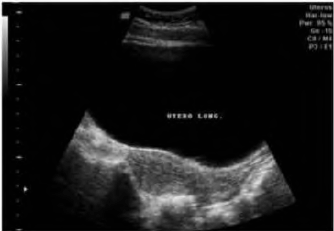

Paciente de 13 anos, com dor pélvica e amenorreia primaria, procura o ginecologista levada por sua mãe. Ao exame pélvico, pode-se observar seguinte achado:

A ultrassonografia pélvica mostrava o seguinte achado:

Qual o diagnóstico dessa paciente?